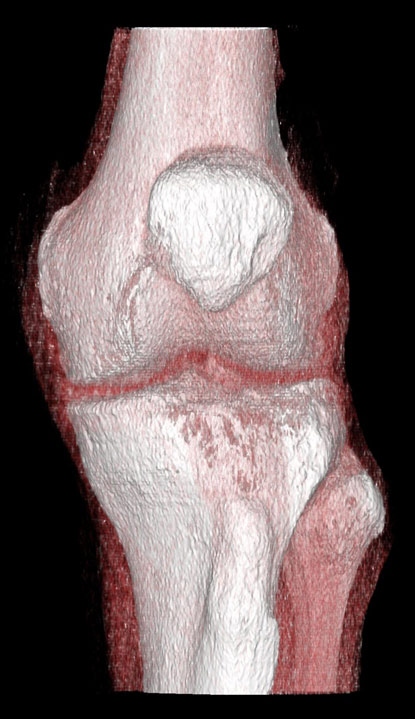

Imaginile cu parametri de părți moi (“kernel” dedicat părților moi) sunt de obicei cu contururi mai line, mai “smooth”, cu “netezirea” artificială a micilor detalii și permit reconstrucții 3D foarte plăcute ochiului, cu aspect anatomic.

Reconstrucții tridimensionale